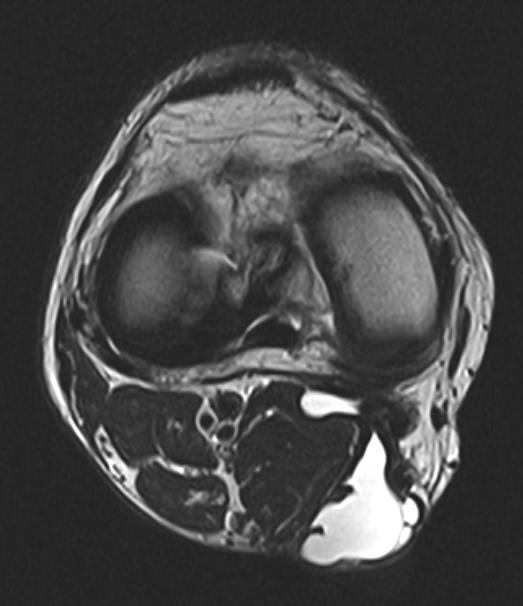

近日,崇州二医院骨三科成功实施一例全关节镜下腘窝囊肿切除术。患者经反复多次切开囊肿切除,术后复发,多次穿刺抽液均没有好转。患者来到二医院骨三科,经科室讨论后选择全镜下切除,手术方案为:采用双后内侧入路,内引流术+囊壁切除。手术施展顺利,目前患者恢复良好,囊肿完全消失。